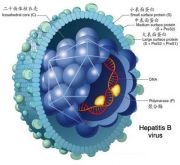

| 2021年7月26日 (一) 20:03 | 乙肝病毒.jpg (文件) |  |

24 KB | Uploaded with SimpleBatchUpload | 3 |